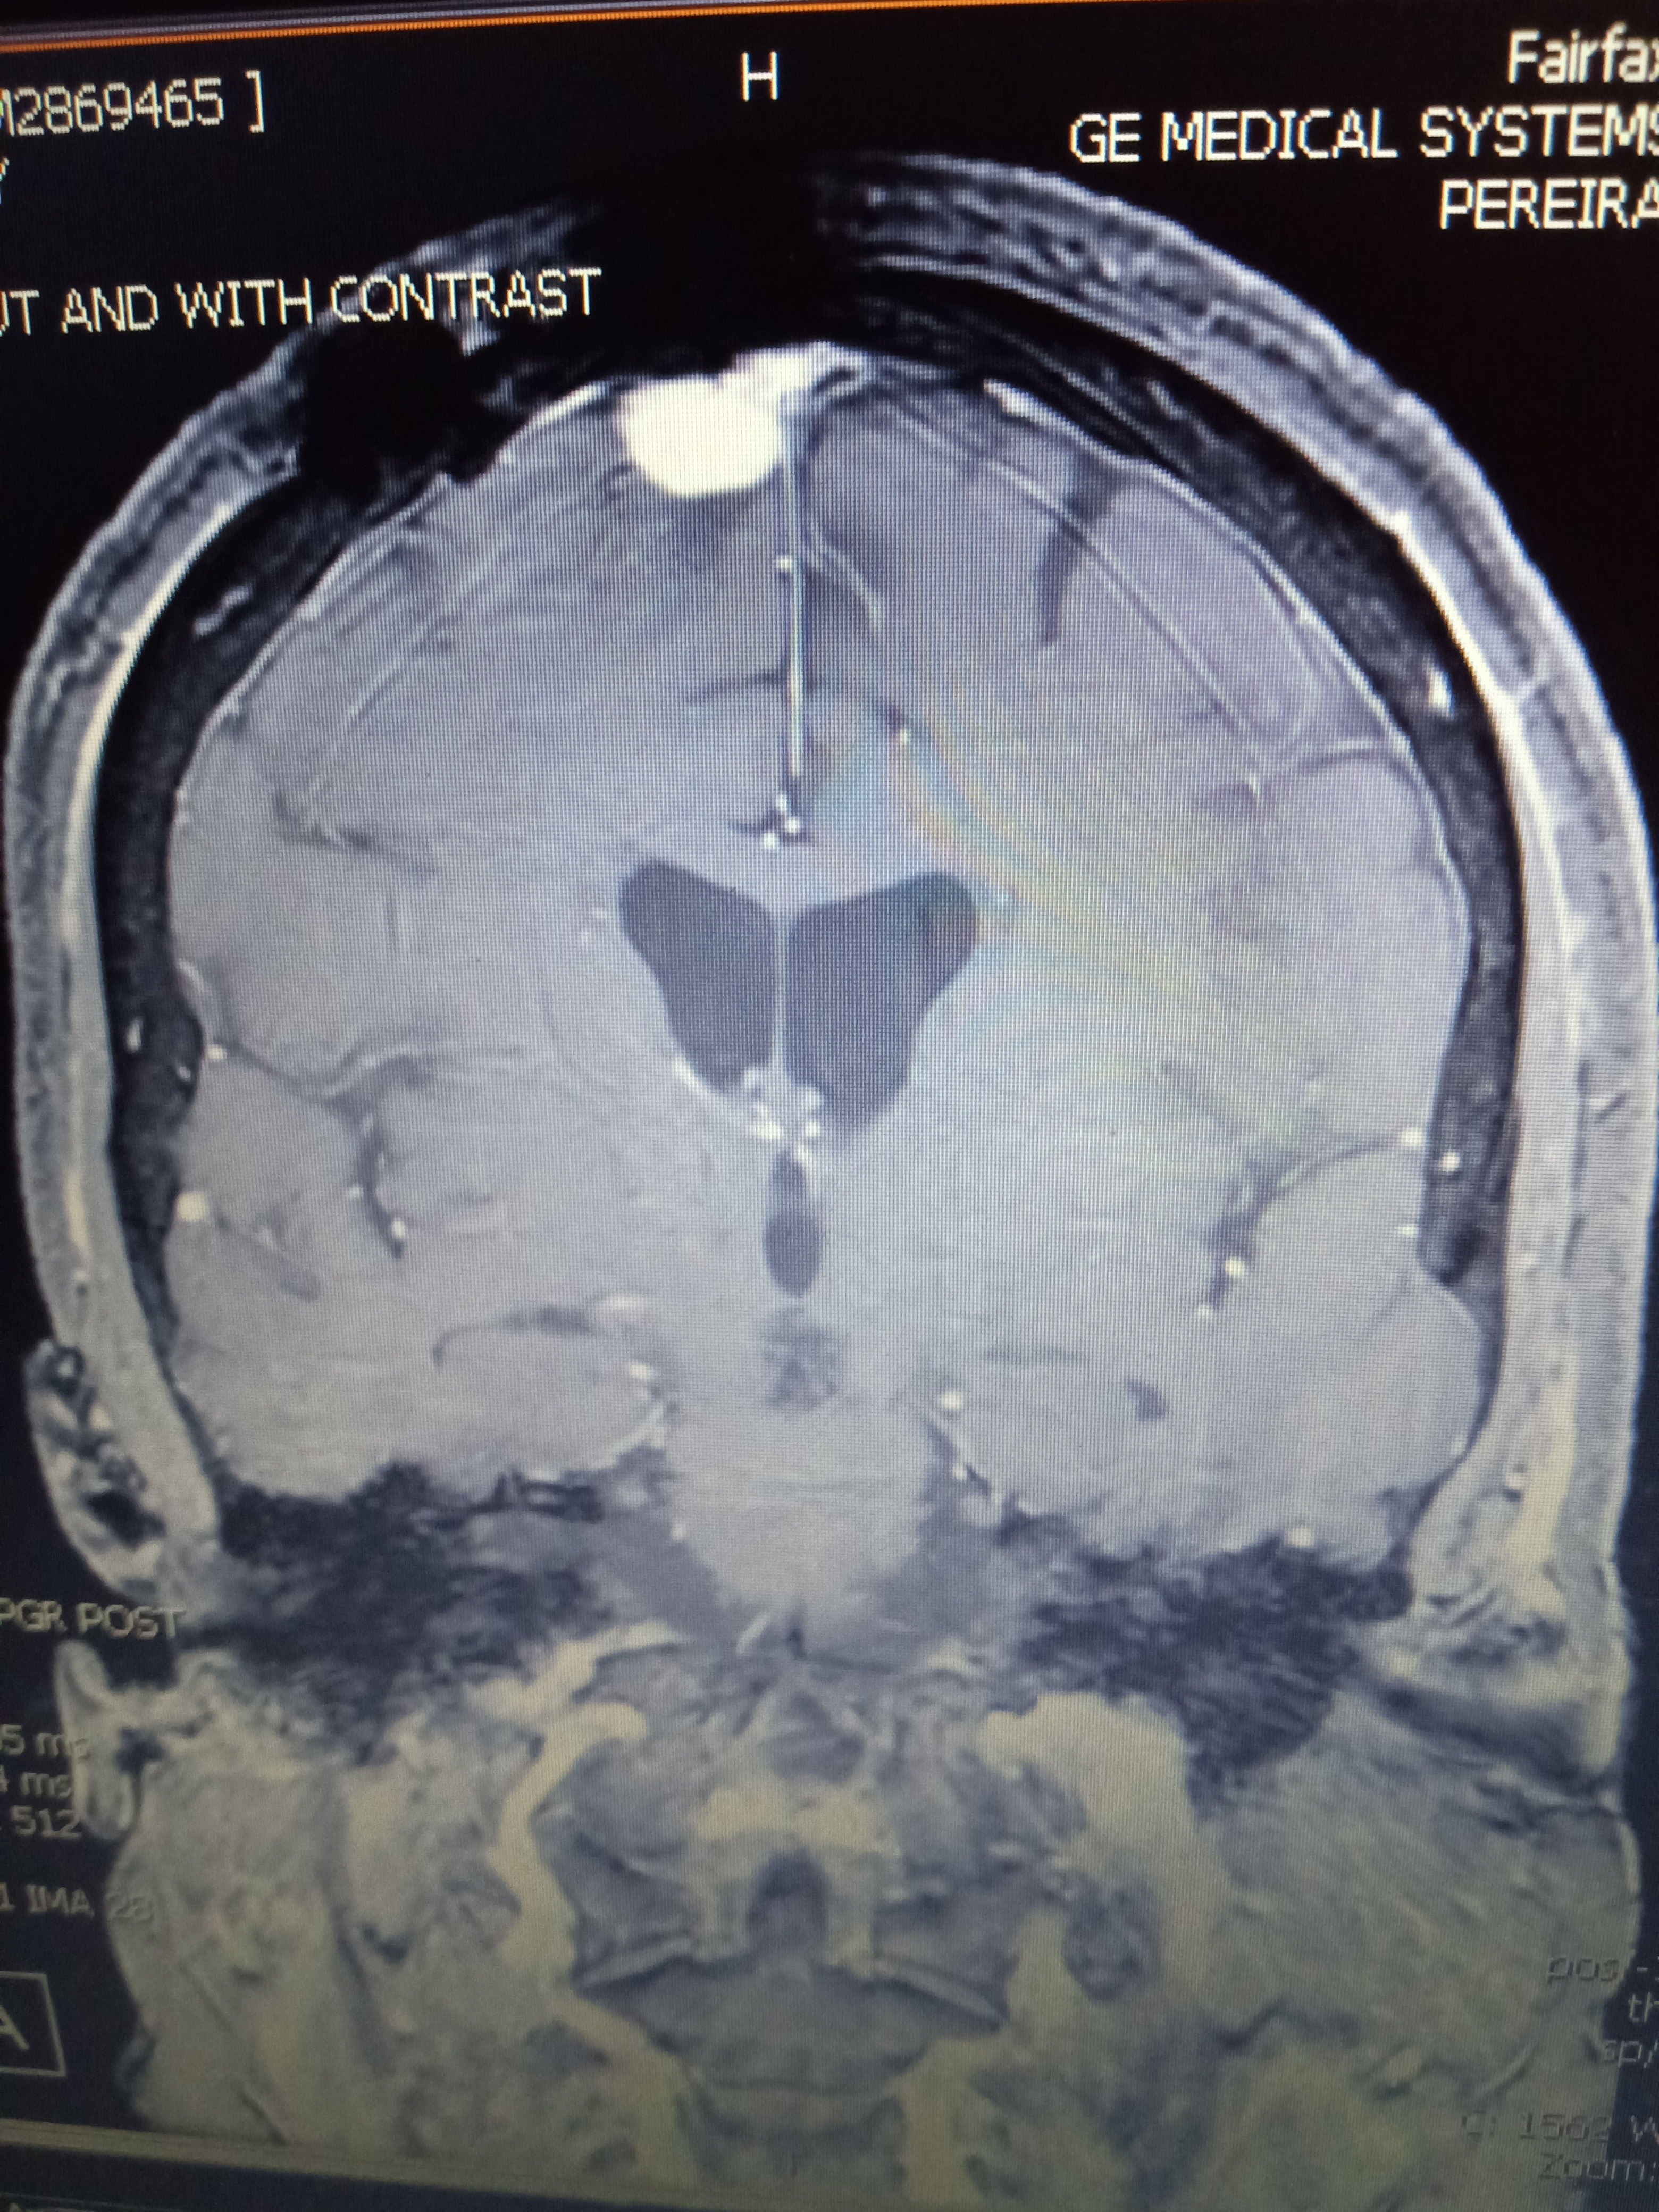

Unfortunately, my brain tumor is growing and with a second craniotomy, location of the tumor, I am likely to encounter more difficulties (possible stroke, more vision loss, more seizures, and more intense falls). I will also need radiation to the remaining tumor to hopefully stunt the possibility of regrowth.

I have also been diagnosed with Parkinson's tremors and right frontal lobe epilepsy. PT and meds are $$$. Everything else is an unknown.